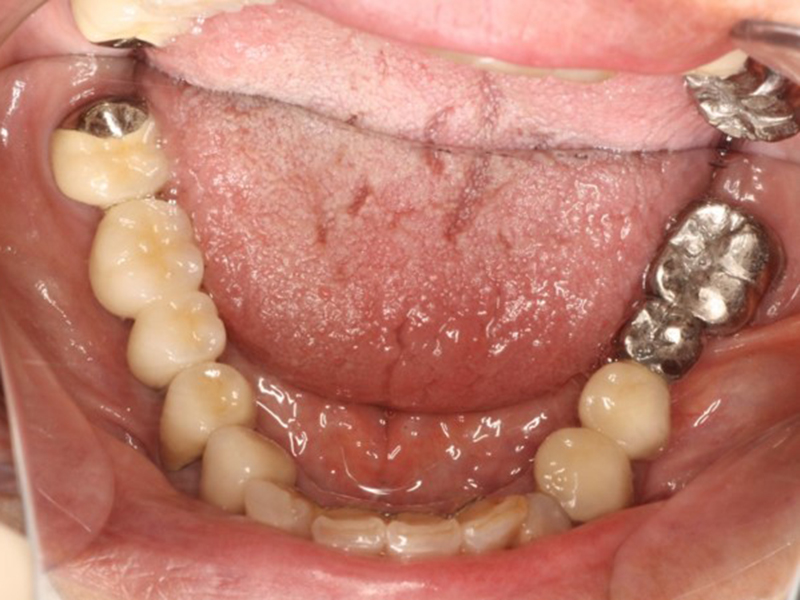

▼ ケース5 下顎前歯部叢生症例

初診時口腔内写真

初診時X線写真